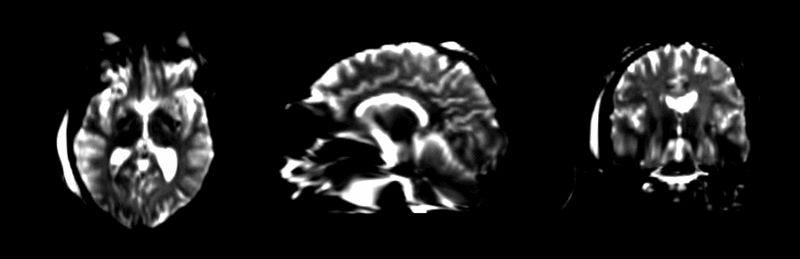

Experiment 2: Co-registration of Subject Specific Multi-modal MRI and DTI

Data before registration.

After affine registration.

After BSpline registration.

After unconstrained diffeomorphic demons.